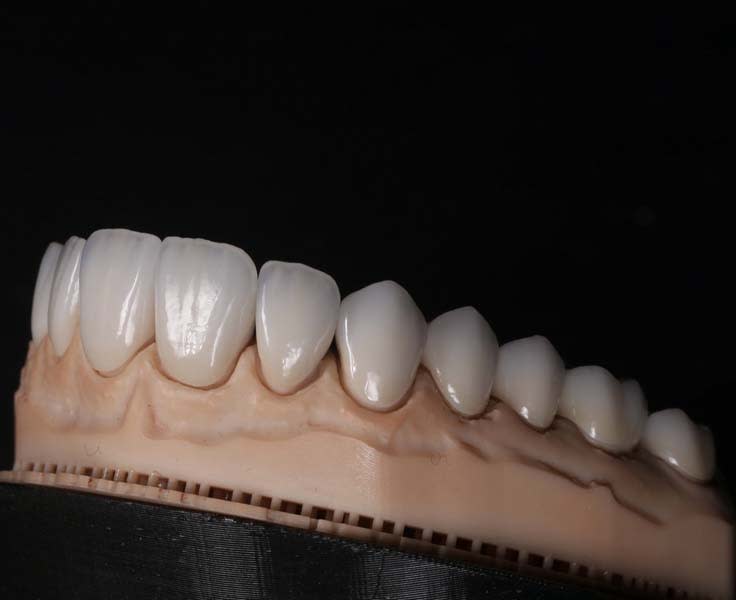

Milled restorations with cut-back designs allowed for optimal esthetic layering.11 To achieve ideal esthetics and incisal translucency, cut-back entailed 0.7 mm to 1 mm buccal reduction from premolar to premolar in both arches and 1 mm incisal reduction for ceramic layering space. Care was taken to ensure smooth transitions between reduced and intact areas. Surface preparation for ceramics after cut-back included air-abrasion with aluminum oxide, ultrasonic cleaning of any residue, and silane primer application for adhesion.

Ceramic layering encompassed four main firings: base dentin layers for core color, opalescent and effect masses at the incisal zone for natural translucency, enamel with enhanced halo at the incisal edges, and, lastly, micro-relief correction and added depth in proximal zones. Each firing stage was accompanied by manual refinement to achieve natural morphology.12 Artistic refinement through post-firing adjustments included proportion corrections, individual light reflection placement per the CAD software plan, and surface texture modeling. Final glazing added gloss without masking the microtexture. Localized polishing was done with diamond pastes for controlled gloss levels (Figure 10 through Figure 12).